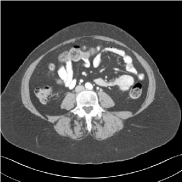

Fig. 2 shows a test example reconstructed using various methods.

Refer to caption

Figure 2: Reconstructions of slice 100 from patient L192 using various methods. The display window is [800 1200] HU.

We observe that PWLS-EP reduces the severe noise and streak artifacts observed in the low-dose FBP images, and the transform learning-based method PWLS-ULTRA further suppresses noise and reconstructs more details of the image such as the zoom-in areas. However, both methods have some blurry artifacts. The standalone FBPConvNet method heavily removes noise and streak artifacts, while introducing several artificial features (e.g., feature indicated by the arrow in the top-right box in Fig. 2). WavResNet denoises the image without introducing artifical features, but still retains some streaks around image boundaries and blurs some details (e.g., feature indicated by the arrow in the bottom-left box in Fig. 2). The state-of-the-art MAP-NN method performs slightly better than WavResNet in terms of suppressing streak artifacts, while it still loses some details as indicated in the zoomed regions. The competing plug-and-play unrolled method—ADMM-Net with WavResNet denoiser—outperforms the standalone WavResNet method, but still has some streak artifacts and blurred details. Compared to these methods, the proposed SUPER methods (SUPER-WRN-EP, SUPER-WRN-ULTRA, SUPER-FCN-EP, and SUPER-FCN-ULTRA) improve the reconstruction quality in terms of removing noise and artifacts, and recovering details more precisely. Two other example comparisons are included in the supplement (Fig. 10 and Fig. 11).